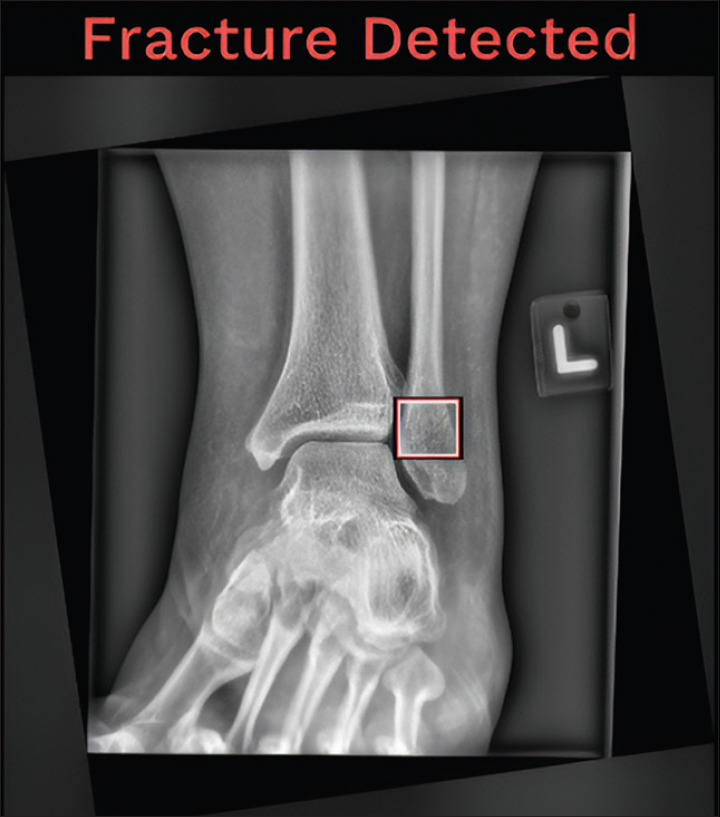

Introduction: Radiology plays an integral role in fracture detection in the emergency department (ED). After hours, when there are fewer reporting radiologists, most radiographs are interpreted by ED physicians. A minority of these interpretations may miss diagnoses, which later require the callback of patients for further management. Artificial intelligence (AI) has been viewed as a potential solution to augment the shortage of radiologists after hours. We explored the efficacy of an AI solution in the detection of appendicular and pelvic fractures for adult radiographs performed after hours at a general hospital ED in Singapore, and estimated the potential monetary and non-monetary benefits.

Methods: One hundred and fifty anonymised abnormal radiographs were retrospectively collected and fed through an AI fracture detection solution. The radiographs were re-read by two radiologist reviewers and their consensus was established as the reference standard. Cases were stratified based on the concordance between the AI solution and the reviewers' findings. Discordant cases were further analysed based on the nature of the discrepancy into overcall and undercall subgroups. Statistical analysis was performed to evaluate the accuracy, sensitivity and inter-rater reliability of the AI solution.

Results: Ninety-two examinations were included in the final study radiograph set. The AI solution had a sensitivity of 98.9%, an accuracy of 85.9% and an almost perfect agreement with the reference standard.

Conclusion: An AI fracture detection solution has similar sensitivity to human radiologists in the detection of fractures on ED appendicular and pelvic radiographs. Its implementation offers significant potential measurable cost, manpower and time savings.